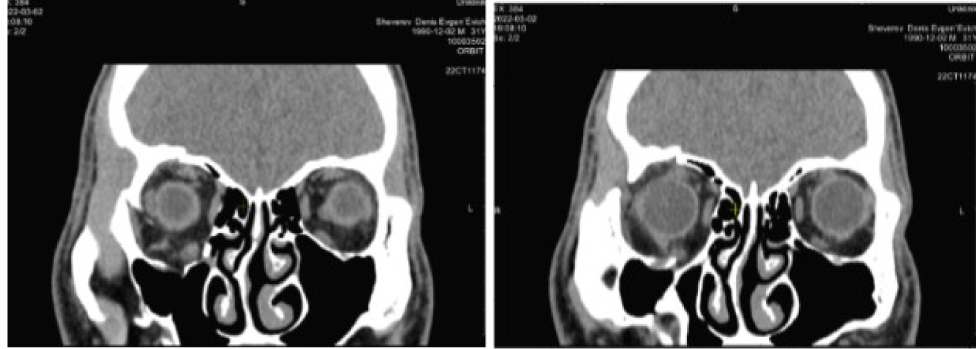

Клинический пример 3. Пациент Ш., 48 лет, обратился с жалобами на несмыкание век правого глаза. Полтора года назад в ДТП получил открытую черепно-мозговую травму, перелом костей лица. Находился в медикаментозной коме. На фоне компрессии лицевого нерва развился нейротрофический кератит. Пациент перенес серию реконструктивных операций на костях лицевого и мозгового черепа, также была проведена репозиция костных отломков правой орбиты с замещением дефектов костными аутотрансплантатами.

На момент обращения выявлен парез лицевого нерва, лагофтальм 5 мм, ретракция верхнего века 2 мм, край нижнего века располагается по нижнему лимбу, стойкое помутнение роговицы в нижней трети. В первичной позиции OD отклонен вверх-кнаружи на 2–3 градуса по Гиршбергу. Подвижность глазного яблока кверху, кнутри и книзу ограничена (рис. 8).

По данным КТ сохраняется расширение объема правой орбиты за счет смещения нижне-внутренней стенки до 10 мм на границе задней трети. Высота нижней стенки локально восстановлена за счет узкого костного трансплантата, расположенного аксиально на границе наружной трети (рис. 9).

Рис. 9. Компьютерная томография орбит до операции. Клинический пример 3

Планируется серия реконструктивных операций. Первым этапом было решено провести реконструкцию орбиты добавочными пластинами в дополнение к костному трансплантату по 3D модели.

В ходе проведения операции с помощью бора удален костный трансплантат, обнаружена и мобилизована разорванная нижняя прямая мышца, сращенная с медиальным краем транспалантата. Визуализированы проксимальный и дистальный отрезки мышцы, оба конца сшиты узловым швом. Составной титановый имплантат помещен в орбиту и фиксирован двумя винтами.